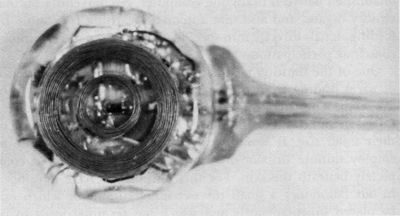

This gap is now being filled, and as Figures 4 and 5 show, it is already possible to equip animals or human beings with minute instruments called "stimoceivers" for radio transmission and reception of electrical messages to and from the brain in completely unrestrained subjects. Microminiaturization of the instrument's electronic components permits control of all param-

eters of excitation for radio stimulation of three different points within the brain and also telemetric recording of three channels of intracerebral electrical activity. In animals, the stimoceiver may be anchored to the skull, and different members of a colony can be studied without disturbing their spontaneous relations within a group. Behavior such as aggression can be evoked or inhibited. In patients, the stimoceiver may be strapped to the head bandage, permitting electrical stimulation and monitoring of intracerebral activity without disturbing spontaneous activities.

One of the limiting factors in these studies was the existence of wires leading from the brain to the stimoceiver outside of the scalp. The wires represented a possible portal of entry for infection and could be a hindrance to hair grooming in spite of their small size. It would obviously be far more desirable to employ minute instruments which could be implanted completely beneath the skin. For this purpose we have developed in our laboratory a small three-channel stimulator which can be placed subcutaneously and which has terminal leads to be implanted within the liraiii (Figure 6). The instrument is solid state, has no batteries, and can work indefinitely. Necessary electrical energy, remote control of parameters of stimulation, and choice of channels are provided by transdermal coupling, using a small coil which is activated by frequency-modulated radio signals. In February, 1969, an experiment was begun in monkey Nona and in chimpanzee Suzi who were equipped with subcutaneous stimulators to activate their brains from time to time for the rest of their lives. Terminal contacts were located in motor pathways in order to evoke flexion of the contralateral leg, an effect simple enough to be observed and quantified without difficulty. Study of Nona and Suzi and preliminary investigations in other animals have demonstrated that subcutaneous instrutiientation is efficient, reliable, and well tolerated. Behavioral responses were consistent, and local motor excitability was not modified by repeated experimentation. Thus the technical problems of stimulating any desired area of the brain for as long as necessary in the absence of conductors passing through the skin have been solved, therapeutic and scientific possibilities have been multiplied, and the comfort of subjects has been considerably increased.